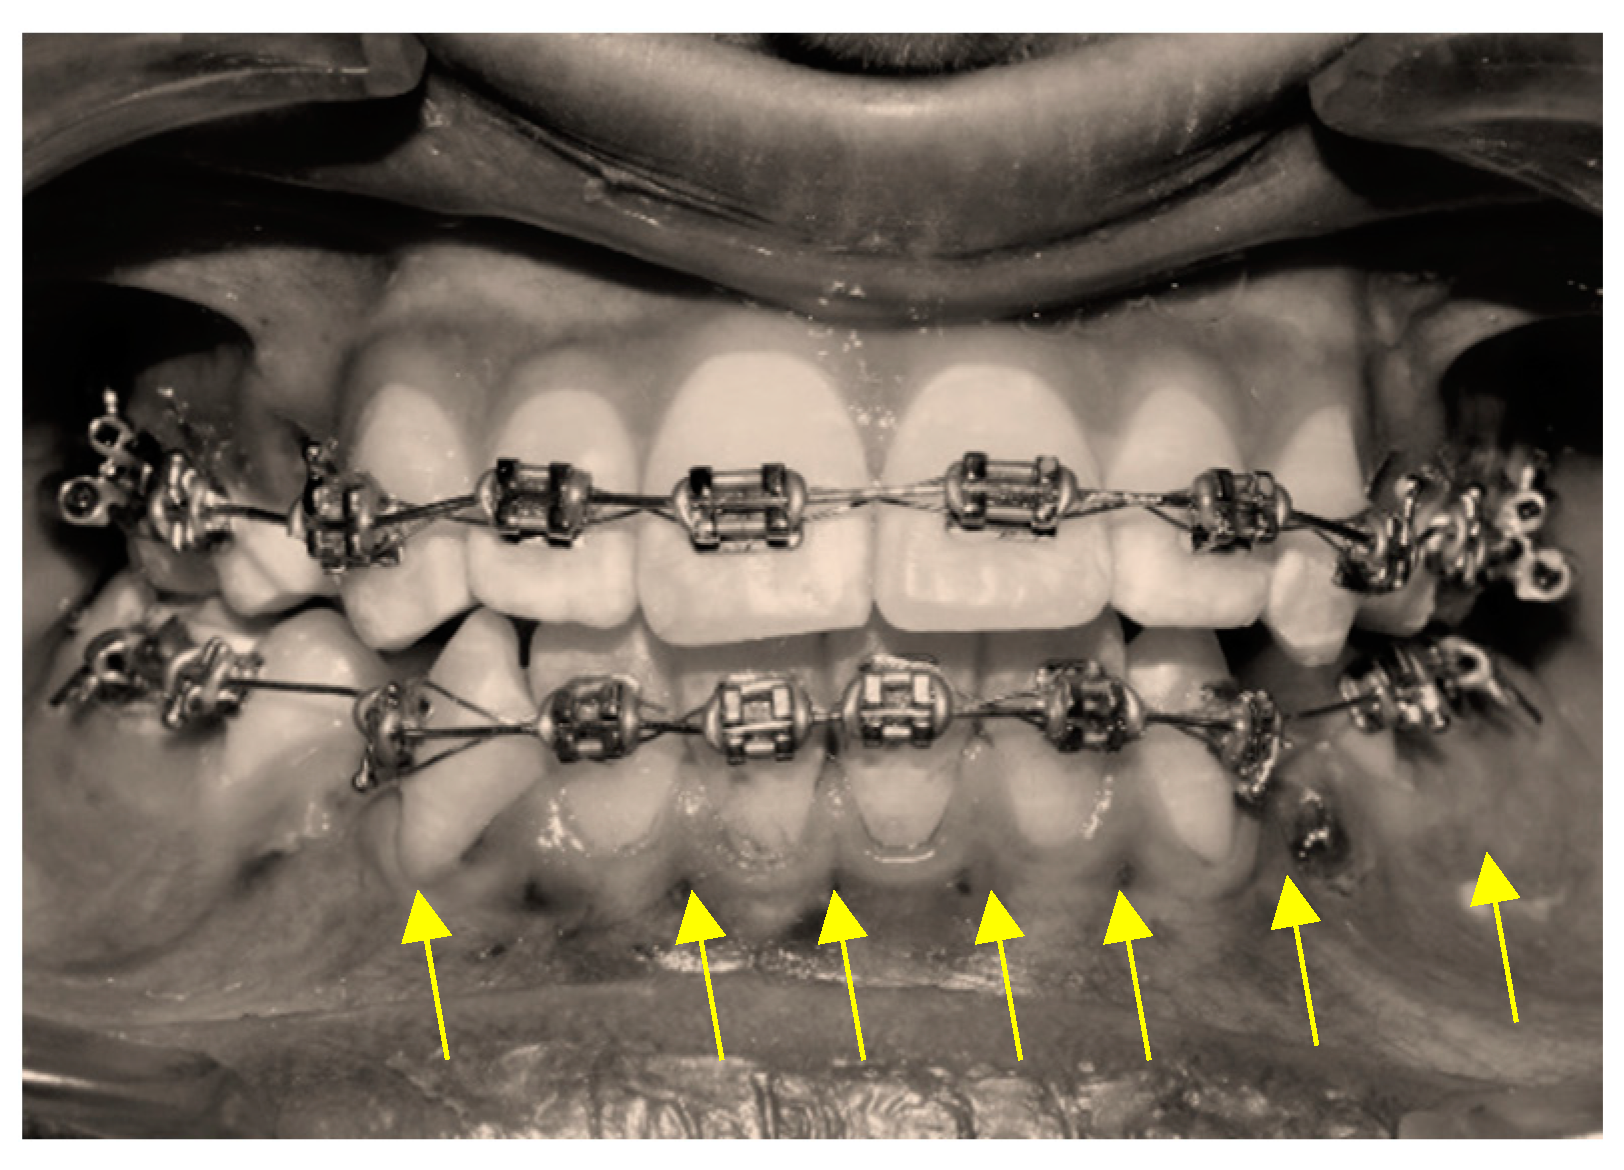

2.3.2. Micro-Osteoperforation Procedure (MOP)